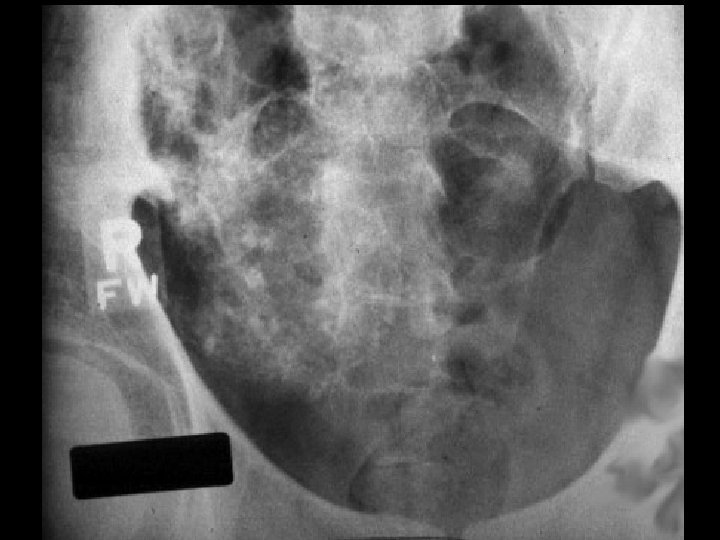

Hemangioma • Findings: – Sclerotic expansile lesion of the right hemipelvis – “Irish lace” appearance on CT • ddx: – NONE! – This is an Aunt Minnie!